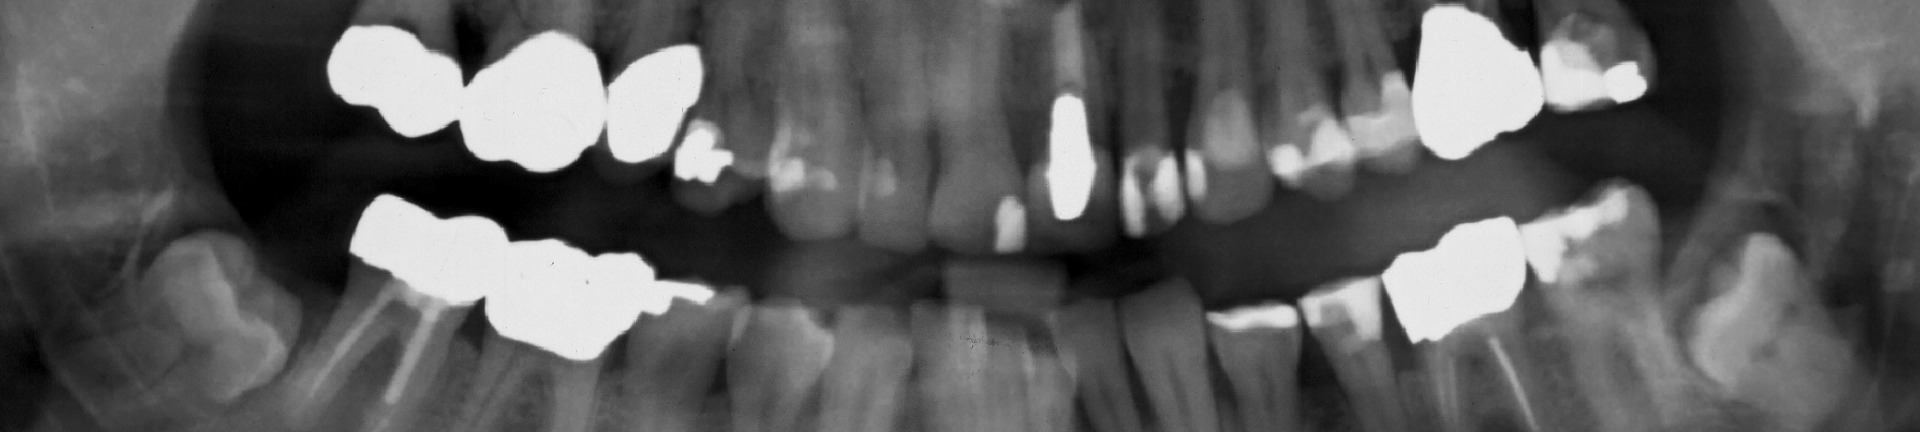

Mechanical testing of teeth has been undertaken to determine the true effects of root canal treatment on tooth structure. This work has been done in collaboration with engineering colleagues at UWA and has been designed to disprove many of the concepts and misperceptions that exist within the profession.

The group has also investigated cracks and their propagation through teeth with engineering colleagues. This work has included clinical studies, simulated clinical studies laboratory studies. It has led to more reliable diagnosis of cracks in teeth, knowledge of how to manage cracks and their effects on the tooth structure and how long-term prognosis and restorative dental needs can be better assessed.